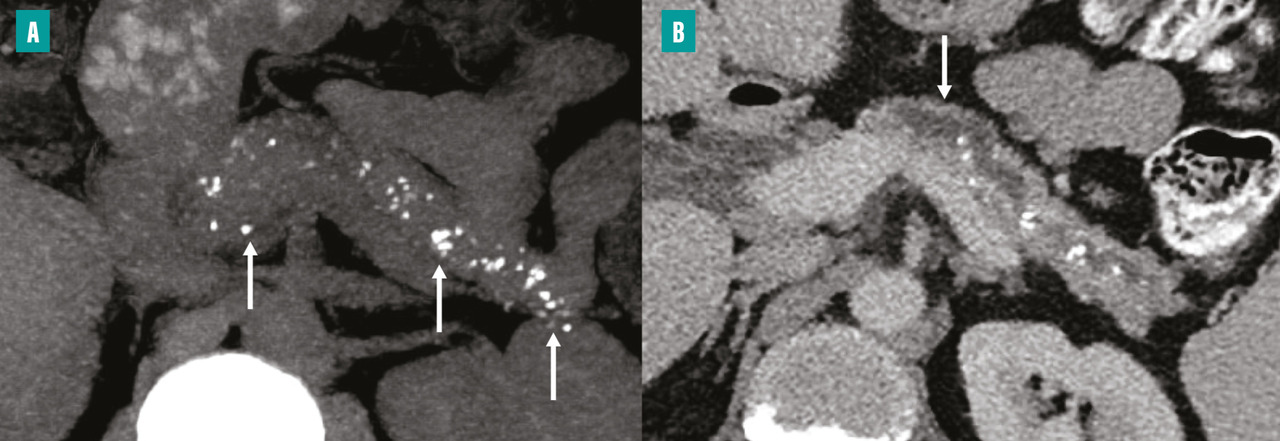

Tomodensitométrie pour identifier des lésions caractéristiques

La tomodensitométrie (TDM) est l’examen initial le plus approprié en cas de suspicion de pancréatite chronique, car elle permet d’identifier des lésions caractéristiques telles que les calcifications parenchymateuses ou des conduits pancréatiques, ainsi que l’atrophie du parenchyme pancréatique. Un protocole TDM optimal comprend des acquisitions sans injection de produit de contraste, une phase artérielle pancréatique (environ 35 à 40 secondes après l’injection) et une phase veineuse (70 à 80 secondes après l’injection). Les calcifications sont facilement détectées sous forme d’hyperdensités spontanées sur les acquisitions sans injection. Elles peuvent être de taille variable. Dans les formes avancées de pancréatite chronique, la TDM peut montrer une dilatation irrégulière du conduit pancréatique principal (fig. 2) et d’éventuelles complications, notamment les pseudokystes et les atteintes vasculaires. La TDM est en revanche moins performante dans les formes précoces de pancréatite chronique, en particulier en l’absence de calcifications. La taille et le nombre des calcifications pancréatiques doivent être évalués, car le degré de calcification dans la pancréatite chronique peut refléter l’évolution et la gravité la maladie.5 La présence de grosses calcifications constitue un signe très évocateur de pancréatite chronique. Cependant, certaines calcifications parenchymateuses pancréatiques liées au vieillissement, généralement ponctiformes (de 1 à 3 mm), ne traduisent pas nécessairement une pancréatite chronique.6